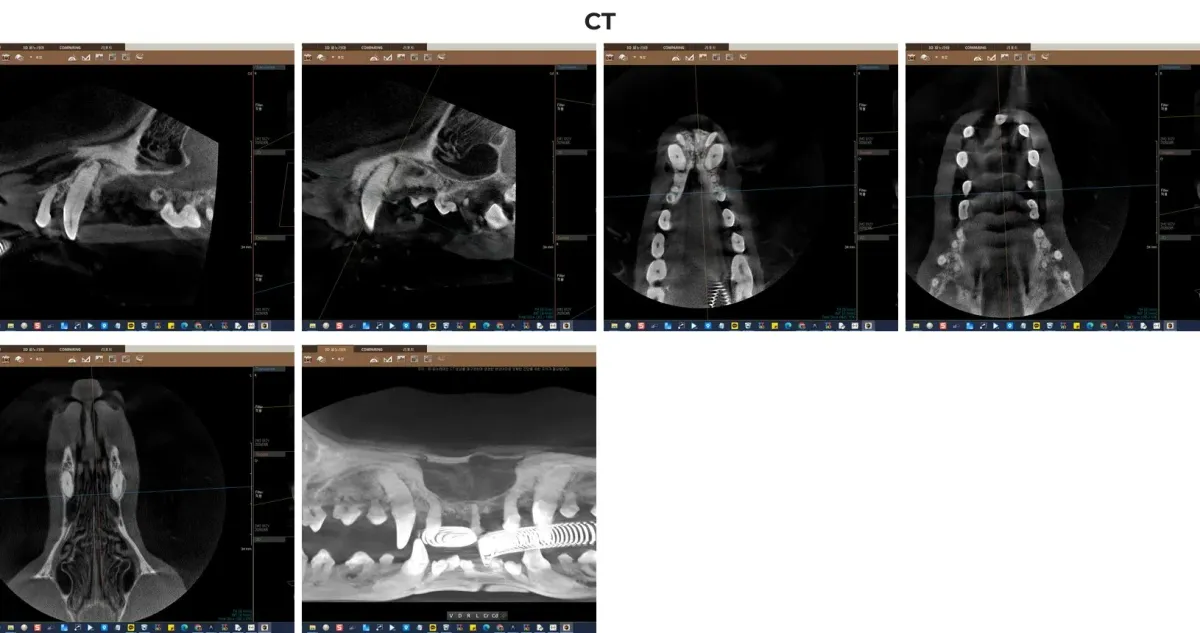

일반적인 구강 방사선만으로는 겹쳐 있는 치아 뿌리나 3차원적인 턱뼈의 소실 정도를 정확히 파악하기 어렵습니다. 특히 만돌이처럼 발치해야 할 치아가 많고 잇몸뼈 손상이 심한 경우(ABL3 단계), 광주 전남 유일 치과 전용 CT 촬영은 선택이 아닌 필수입니다. CT를 통해 치근단 농양의 위치, 신경관과의 거리, 턱뼈 골절 위험도 등을 밀리미터 단위로 파악하여 안전한 수술 계획을 수립할 수 있습니다.

광주 전남 유일 치과 전용 CT를 활용한 만돌이의 3D 턱뼈 및 치근단 평가 영상

만돌이는 중증 치주질환(Periodontal Disease)으로 진단되었습니다. 이미 5개의 치아는 결손(Missing) 상태였으며, 남아있는 치아 중 무려 27개의 치아가 기능 상실 및 심각한 통증을 유발하고 있었습니다. 특히 상악과 하악의 전치부(앞니)부터 구치부(어금니)에 이르기까지 광범위하게 치조골 소실 3단계(ABL3, Alveolar Bone Loss Level 3)가 진행되어 살릴 수 있는 치아가 거의 없는 절망적인 상태였습니다.